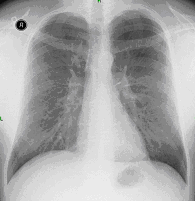

23. Pulmonary metastases, bidirectional (PA and right lateral) plain chest radiograph.

51 year old woman, endometrial carcinoma. Numerous ring shadows bilaterally in basal dominance (max. appr. 12 mm). Left pleural effusion of one finger wide.